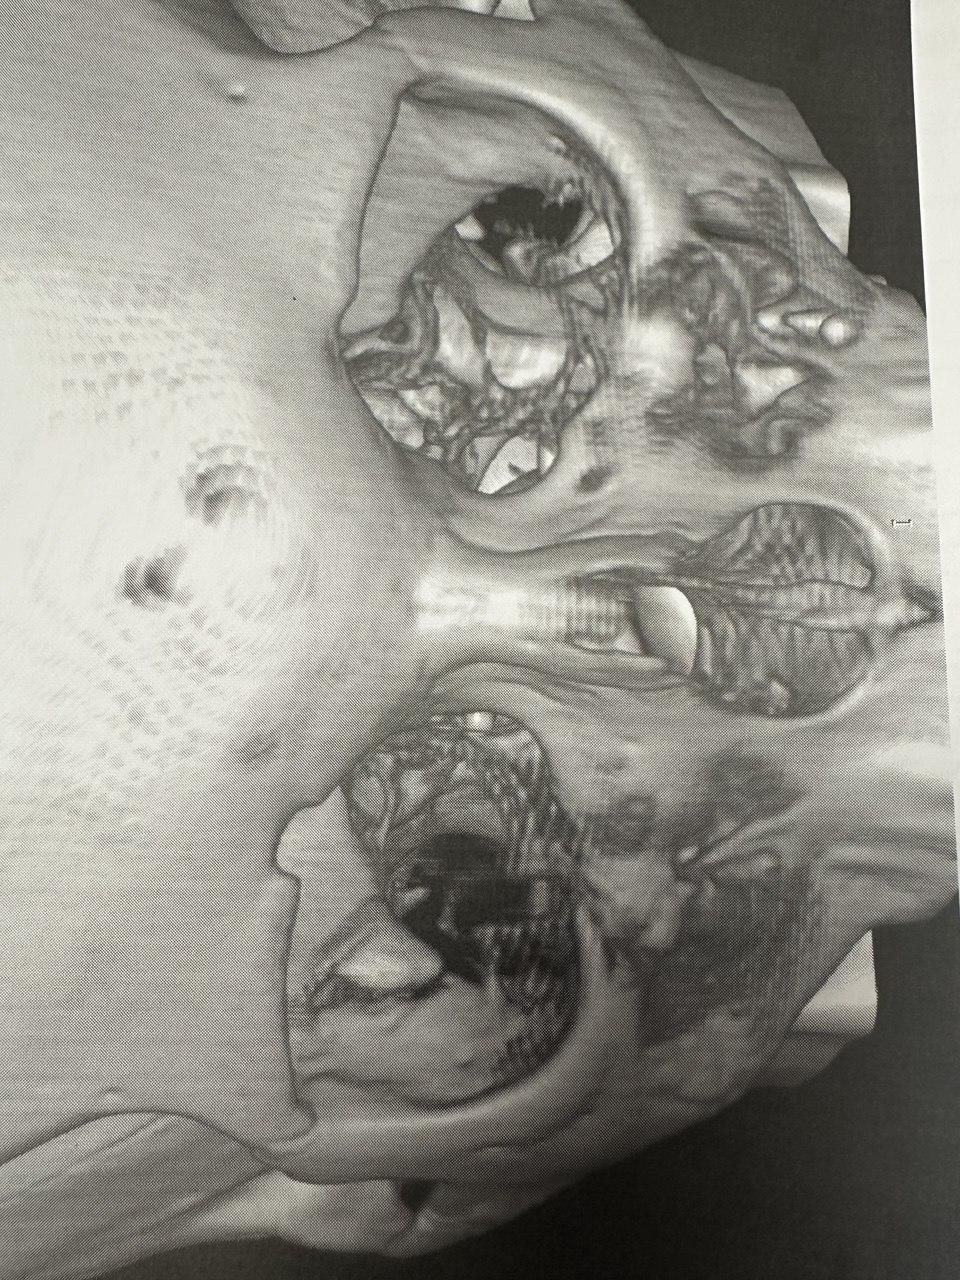

Мальчик получил перелом глазницы в результате драки.

Рентгеновский снимок лицевых костей пострадавшего подростка.

Подростка доставили в больницу. Хирургического вмешательства удалось избежать, но состояние его тяжелое. «У него большая трещина, причем перелом осколочный, осколок остался в глазнице. Он заикаться стал. Даниил раньше запинался, когда волнуется, а сейчас он даже двух слов сказать не может, зуб на зуб не попадает. Парень в шоке, в пришуганном состоянии. Голова болит, потому что сотряс серьезный», — описывает последствия отец.